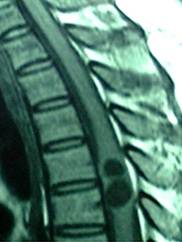

Figure 1

Sagittal T1, T2-weighted MR image of thoracic spine showing a relatively well defined cystic intramedullary lesion with hypointense on T1WI and hyperintense on T2WI.

A 40-year-old female patient was transferred to our department from a local hospital for progressive weakness in both lower limbs for one month, and anal sphincter and bladder dysfunction for two days. Neurological examination disclosed spastic paraparesis with decreased motor power of grade 3/5 in both lower limbs, impaired sensations below T4 dermatome, brisk tendon jerks and positive Babinski signs on both sides. Non-contrast MRI revealed two well-defined round intramedullary cystic lesions at T4 and T5 vertebral levels, which were homogeneously hypointense on T1WI and hyperintense on T2WI with slightly peripheral edema. The subarachnoid space from T4 to T5 was narrow due to the marked expansion of spinal cord. There were no abnormalities at cervical or lumbar levels or within the brain parenchyma. The diagnosis of intramedullary mass lesion was made. There is no use of dexamethasone in the perioperative period.

Cysticercosis is widely endemic in Brazil, Peru, Mexico, Korea and India19-20. Intramedullary cysticercosis often presents in the patients between 20 to 45 years old, with the youngest one 5 years old and the oldest one 45 year's old15. Most patients experienced a progressively worsened course from a week to 10 years20. The common clinical manifestations included pain, paraparesis, spasticity, bowel and bladder incontinence, and sexual dysfunction1,20. However, inflammatory reaction against the dead parasite is associated with perilesional edema, which can damage medullar parenchyma and therefore, worsen symptoms2. Inside the spinal cord, cysticercus usually distributes in the thoracic cord, with a few cases involving the cervical and the lumbar cord. This distributional mode of cysticercus supports the hypothesis that intramedullary cysticercus comes from the blood circulation, because thoracic cord has much more blood supply than the other parts of the spinal cord6,20. However, it is also thought that intramedullary cysticercus could migrate to the spinal cord via the ventriculo-ependymal pathway. On MRI, intramedullary cysticercosis usually show a cystic lesion within the spinal cord, which of appears hypointense on T1WI with hyperintense scolex identified inside the cyst cavity, hyperintense on T2WI in vesicular stage, a subtle hypointense rim may surround the intramedullary cyst on T2WI. In the colloidal stage the thickened cyst capsule is hyperintense on T1WI and hypointense on the T2WI. Cyst contents appear hyperintense on T1WI resulting in scolex is not seen. There is an amount of surrounding edema. If cyst degeneration is present peripheral ring enhancement may be present1,2,15,17. The differential diagnosis of an intramedullary cystic lesion is extensive, including some other cysts such as arachnoid cyst14, ependymal cyst10, neurenteric cyst18, sarcoidosis4, neoplasms such as ependymoma, and infections such as abscess21.